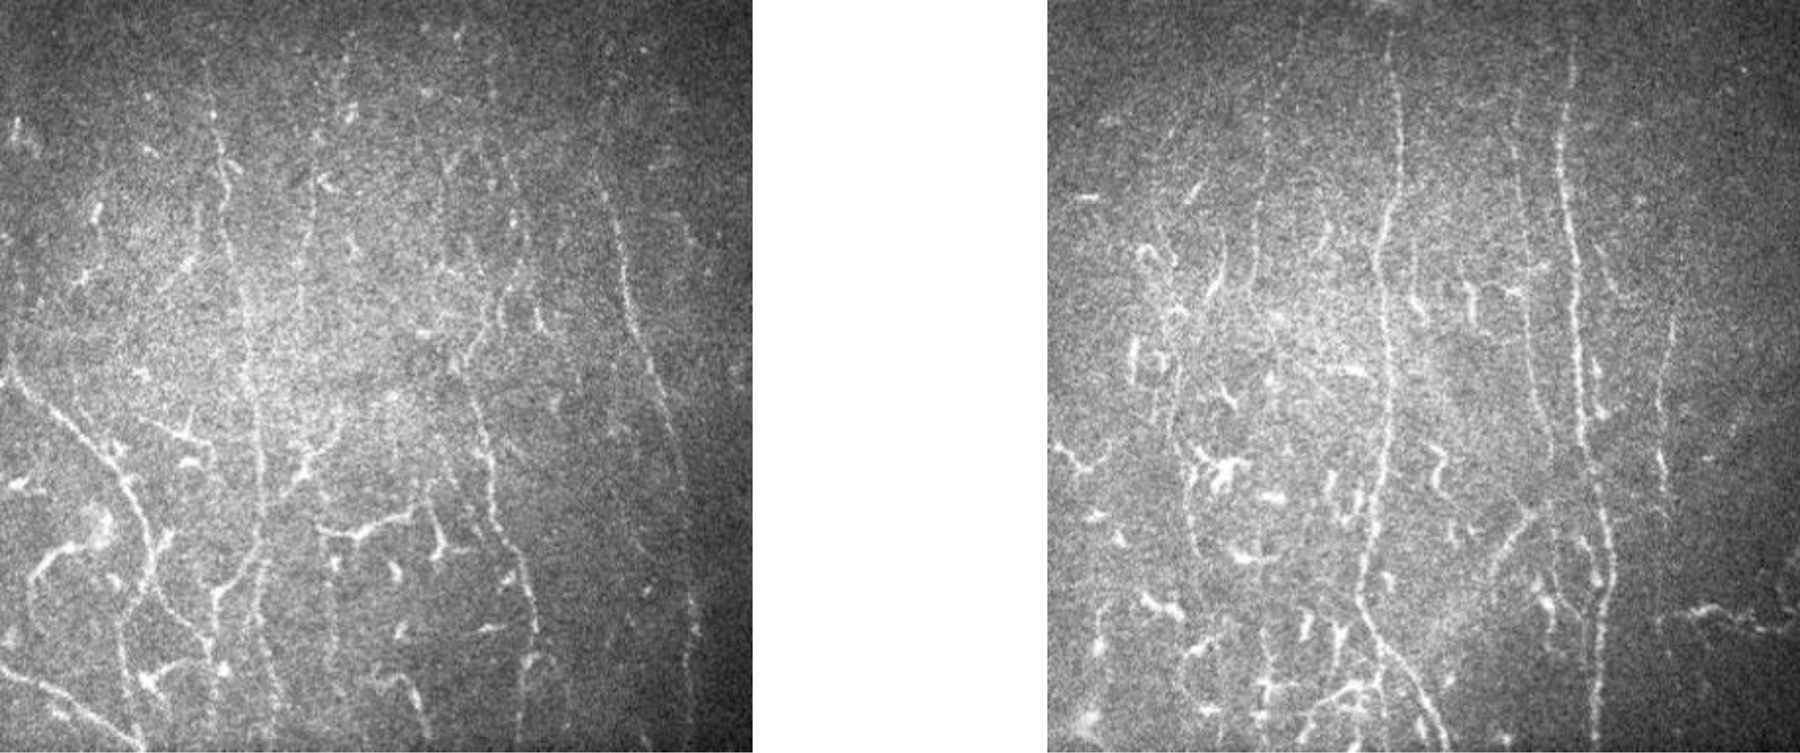

Figure 3:

Examples of neuromas found in SjD participant montages.

Examples of increased nerve tortuosity found in SjD participant montages.

In this study, we investigated features of short fiber neuropathy in SjD using in-vivo confocal microscopy. Participants classified as SjD had markedly lower nerve metrics when compared to healthy controls, a frequently absent central whorl and the presence of neuromas. The presence of neuromas showed the best reliability between graders and may be a differentiating clinical feature between SICCA participants and healthy controls. Luzu et. al found a statistically significant increase of neuromas in their Sjogren’s Disease group compared to controls in their retrospective case-control study.14 They also found reduced density of nerves in the sub-basal nerve plexus and increased tortuosity. These signs taken together can point to an underlying neuropathy.